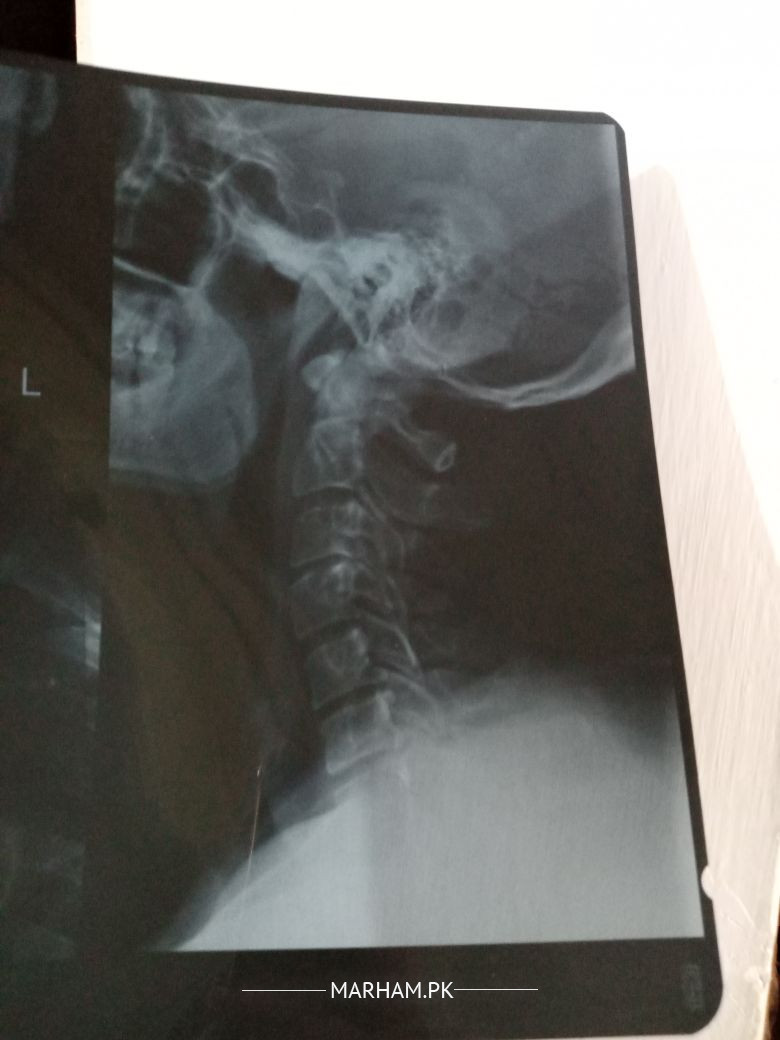

Talk to Radiologist on Neck Xray

Asking for Father Male 58 , Islamabad

Can someone please study these xrays. And point out the problem if any. Kindly tell the specialist needed for this

Patient has stiffness and pain in neck

little bit of straightening of spine and reduced space between C3 and C4